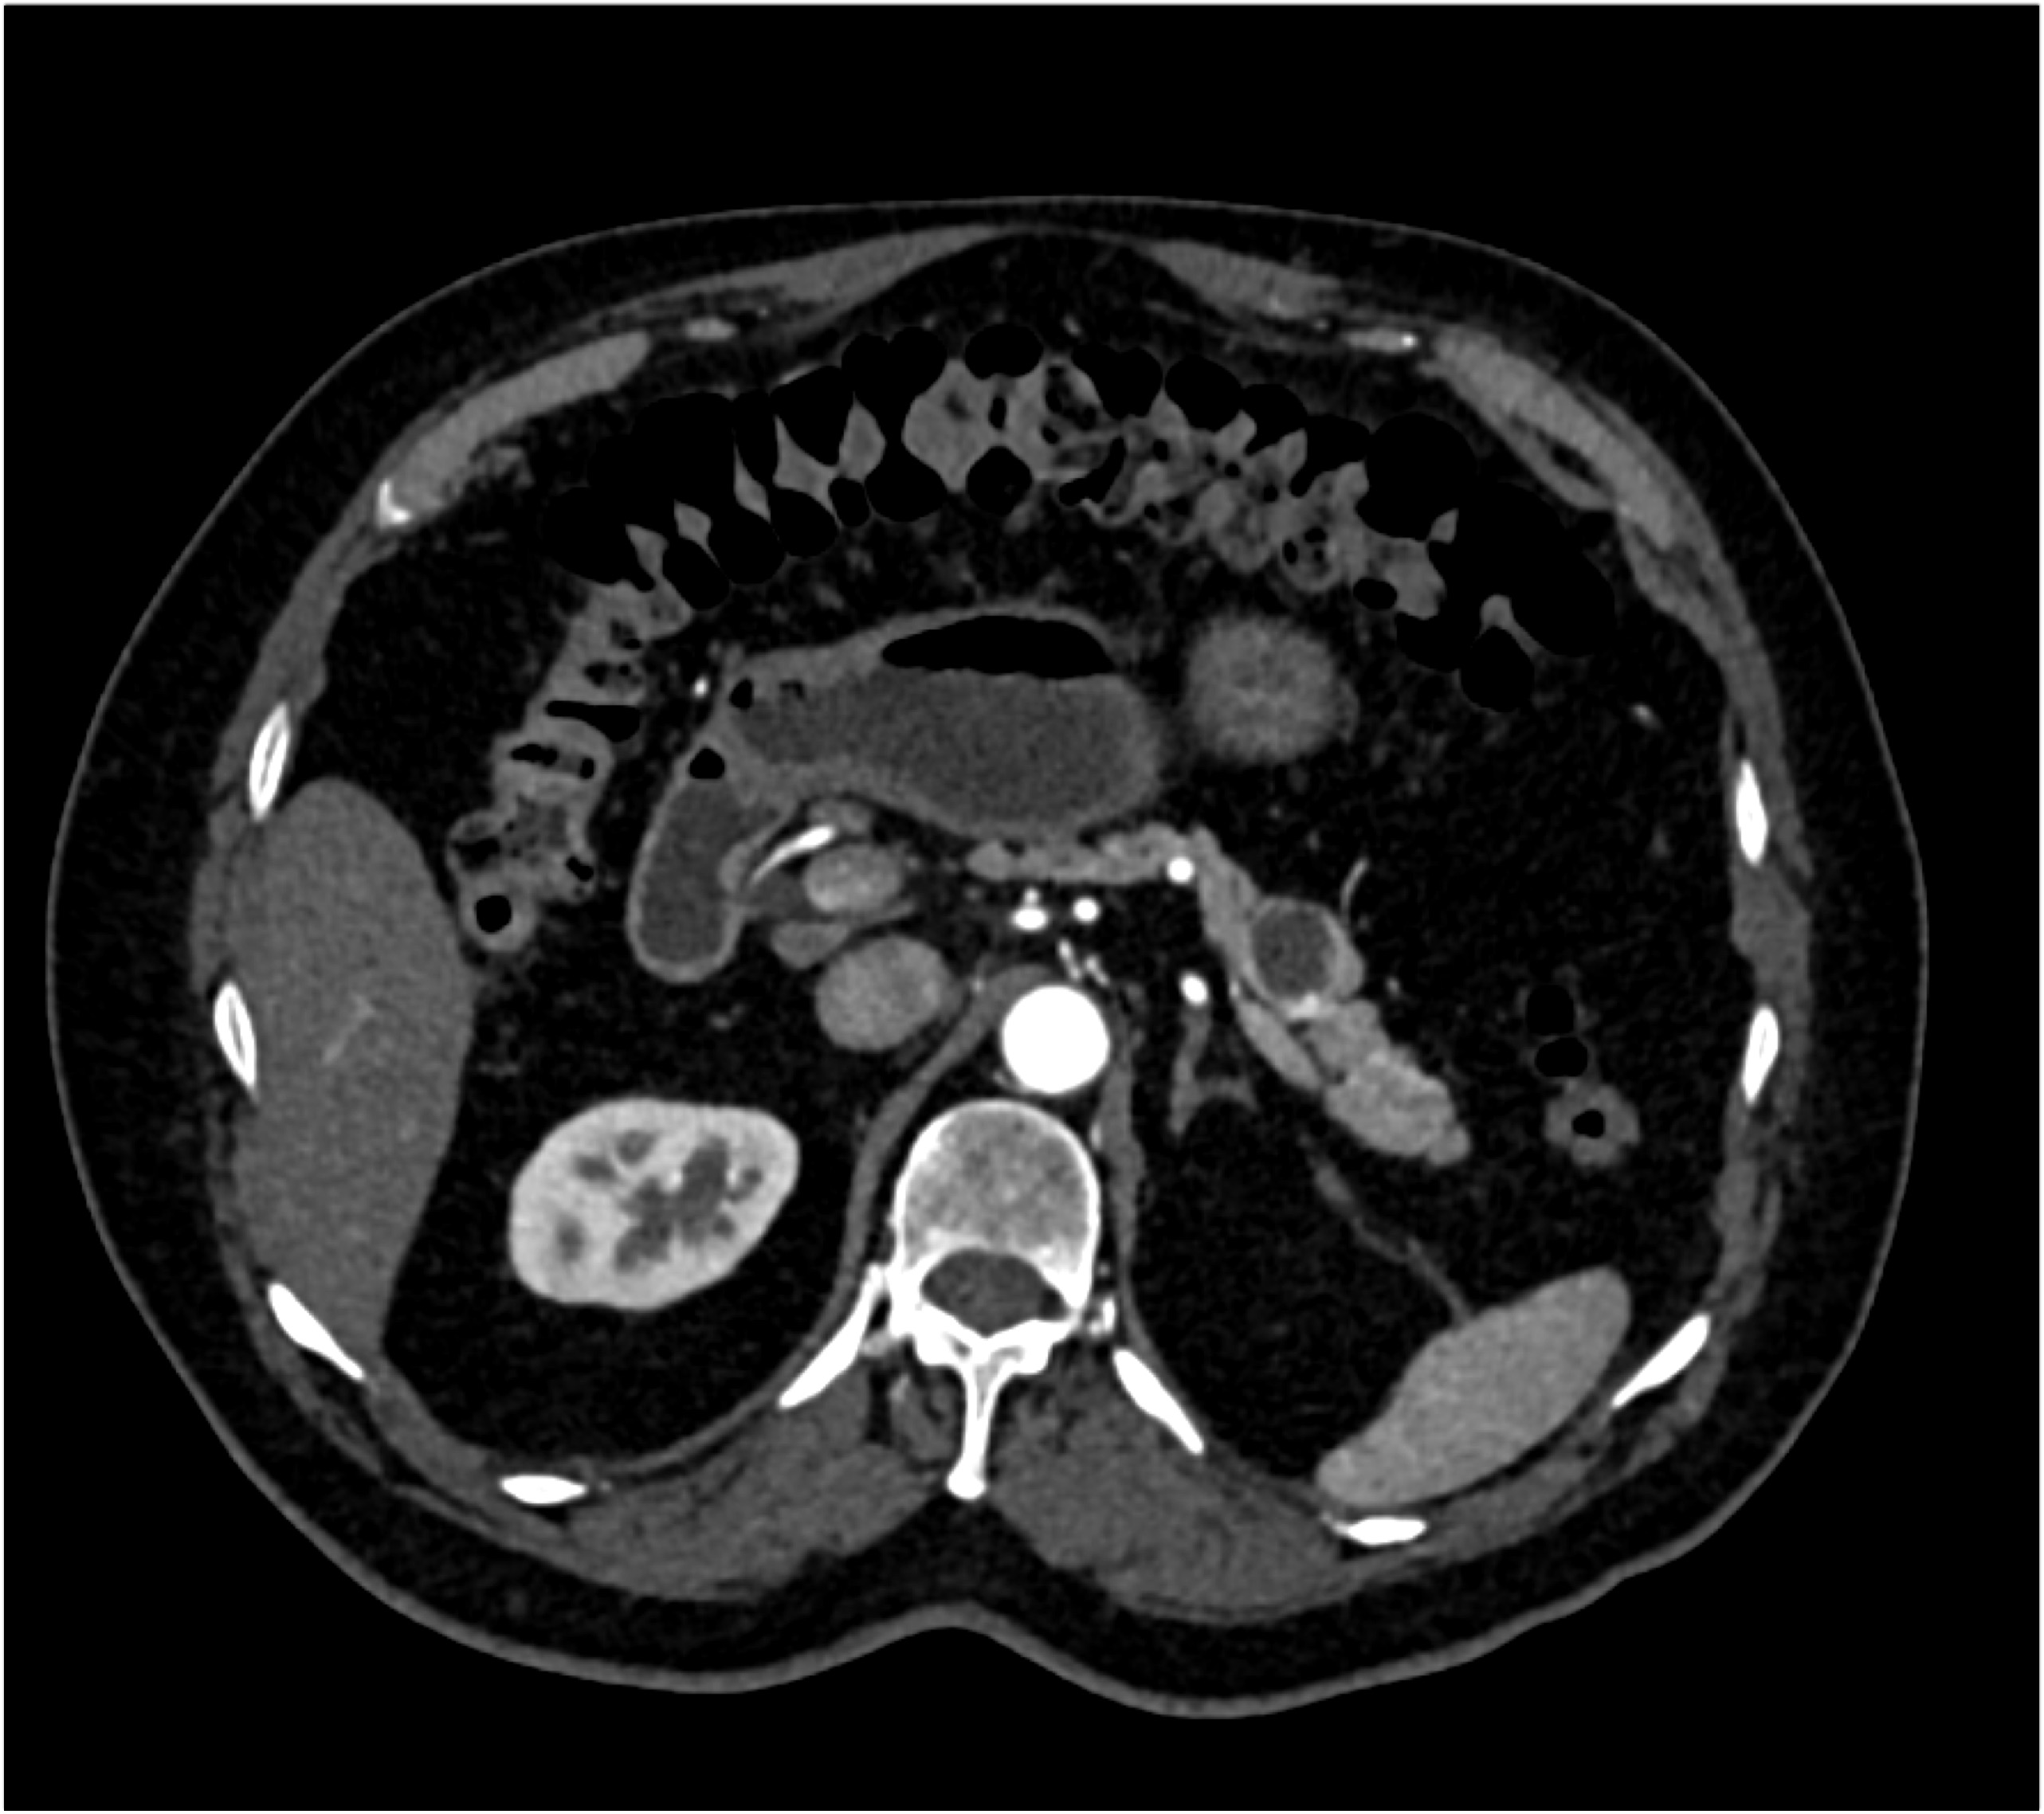

7) The most likely diagnosis in this patient with back pain is?

adrenal adenoma

adrenal hemorrhage

adrenal hyperplasia

adrenal metastases